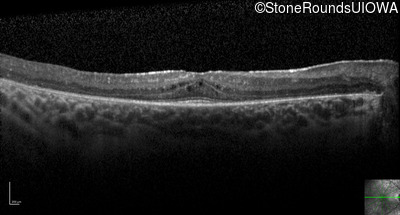

Optical Coherence Tomography - Left - 20/32 +1

Exemplar / OCT Stack

OCT Stack